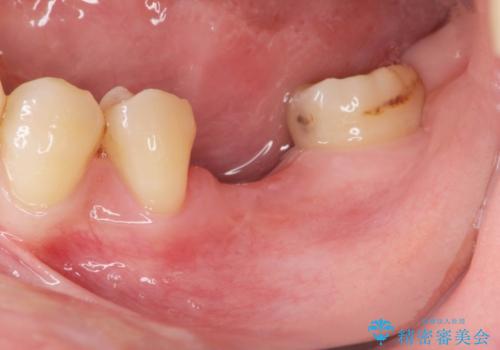

歯槽堤保存を併用し清掃性を高めたブリッジ治療

担当医 大元洋佑